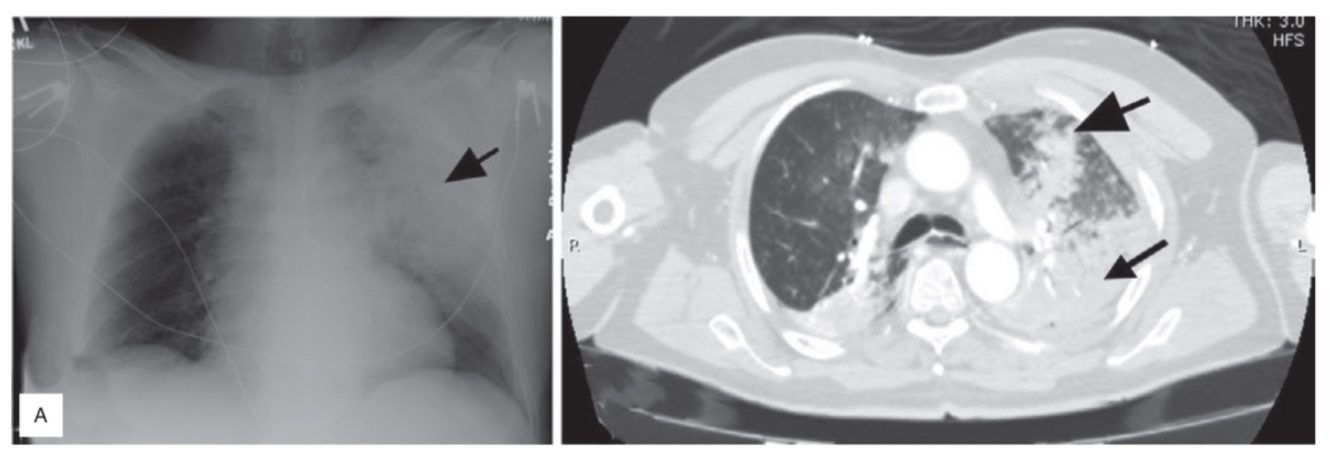

Contusão Pulmonar

1) Contusão pulmonar